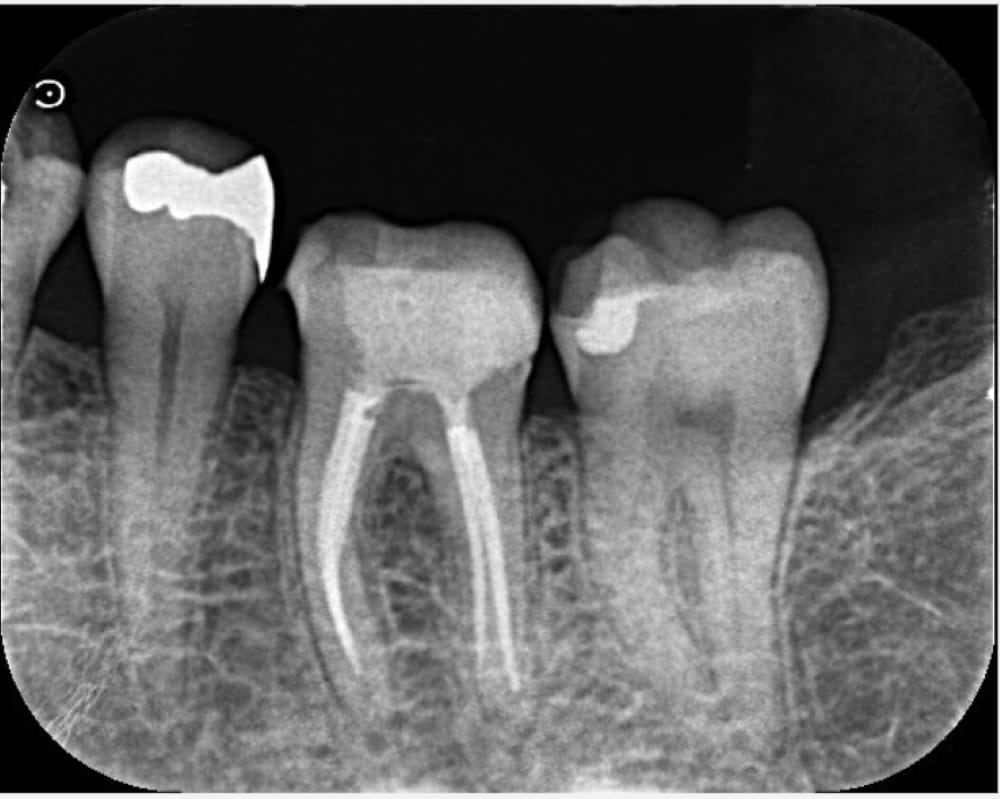

6ヶ月後の経過観察

根管治療から6ヶ月が経過し、普段の痛みは消失したとのことでした。この時点では噛み合わせても上の歯と当たらないように高さを落としている状態ですが、食べ物が当たると強く響くのが心配とのことなので、追加で6ヶ月(術後12ヶ月まで)経過観察となりました。